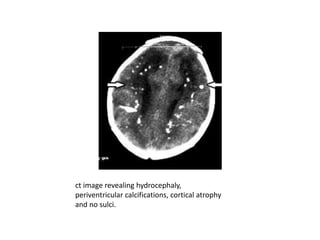

ct image revealing hydrocephaly,

periventricular calcifications, cortical atrophy

and no sulci.

• Toxoplasmosis infection is multifocal and

scattered. CT and MR scans most often

demonstrate calcifications that can involve the

periventricular regions, basal ganglia or

peripheral cerebral tissue

• Hydrocephalus can be seen

• Nonspecific findings include atrophy,

encephalomalacia, hydranencephaly or

microcephaly